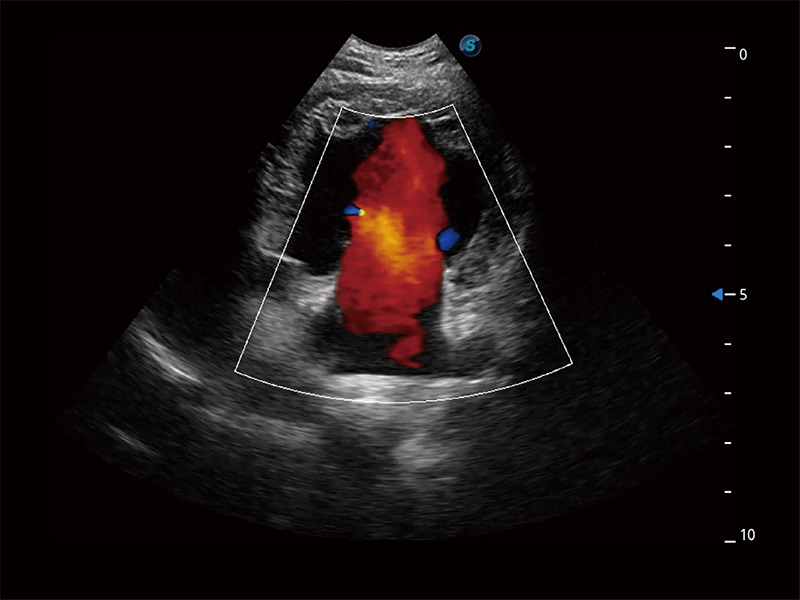

極大提升超低速微細(xì)血流的檢出能力,同時(shí)更精準(zhǔn)地濾除軟組織和超聲信號(hào),為獸用醫(yī)生提供以往無(wú)法通過(guò)常規(guī)血流獲得的疾病診斷信息。

在傳統(tǒng)二維血流成像的基礎(chǔ)上,呈現(xiàn)血流的立體感,具有動(dòng)感的生命力之美。即便是微小的血管也能輕松應(yīng)對(duì),提高了血流的視覺(jué)敏感性。